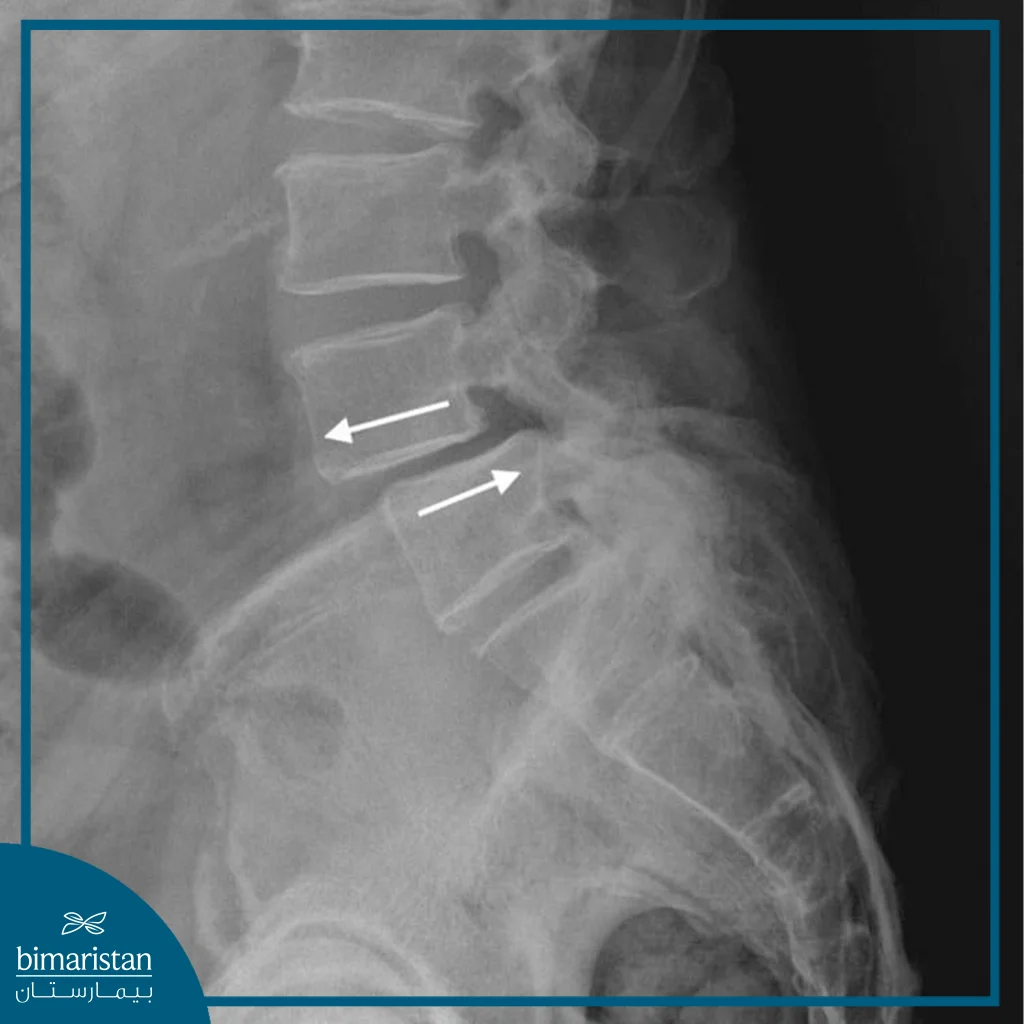

Lumbar stabilization surgery is a surgical procedure used to treat spinal issues in the lower back (lumbar region), which may include herniated discs, fractures, or degenerative diseases such as arthritis. The procedure aims to restore stability to damaged vertebrae by fusing them together using metal instruments such as pins and rods. The primary goal of lumbar stabilization surgery is to relieve pain caused by the spinal disorder and improve spinal function, helping to restore normal mobility.

- Installing the metal pins and rods: The surgeon attaches the metal pins to the targeted vertebrae and then attaches them to the rods to ensure spinal stability, making sure the vertebrae are properly aligned to prevent any future deformity.

- Check for stability and alignment: The surgeon uses imaging during the procedure to make sure that the screws and rods are in place and the vertebrae are perfectly aligned to avoid any later complications.

In the following weeks, radiographs are taken to ensure that the screws and rods are stable and the vertebrae are properly aligned, and a physical therapy program is prescribed to strengthen the muscles surrounding the spine and improve flexibility. Regular follow-up is essential to ensure the success of the procedure and minimize any potential complications. It also helps to assess the patient’s progress and adjust the treatment program as needed to ensure the best possible outcome and return to normal daily activity.